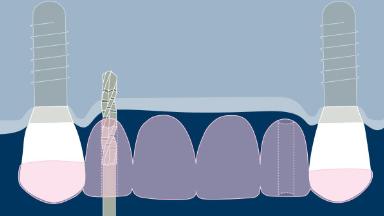

This clinical image shows three adjacent implants supporting single crowns. These provided the patient with a good functional outcome, but esthetics at the level of the implant emergence was only a secondary consideration.

In modern implant dentistry, the overall esthetic result is of equal or greater importance to the patient. Esthetic results are closely related to a high level of accuracy in the positioning of the supporting dental implants.

A second clinical image shows an example of an implant-supported single crown on the upper left central incisor where careful implant positioning has allowed the emergence profile to mimic that of the natural right central incisor.

Templates to guide accurate three-dimensional implant placement are critical to achieving such an outcome. This ITI Learning Module will discuss routine use of templates in implant therapy.